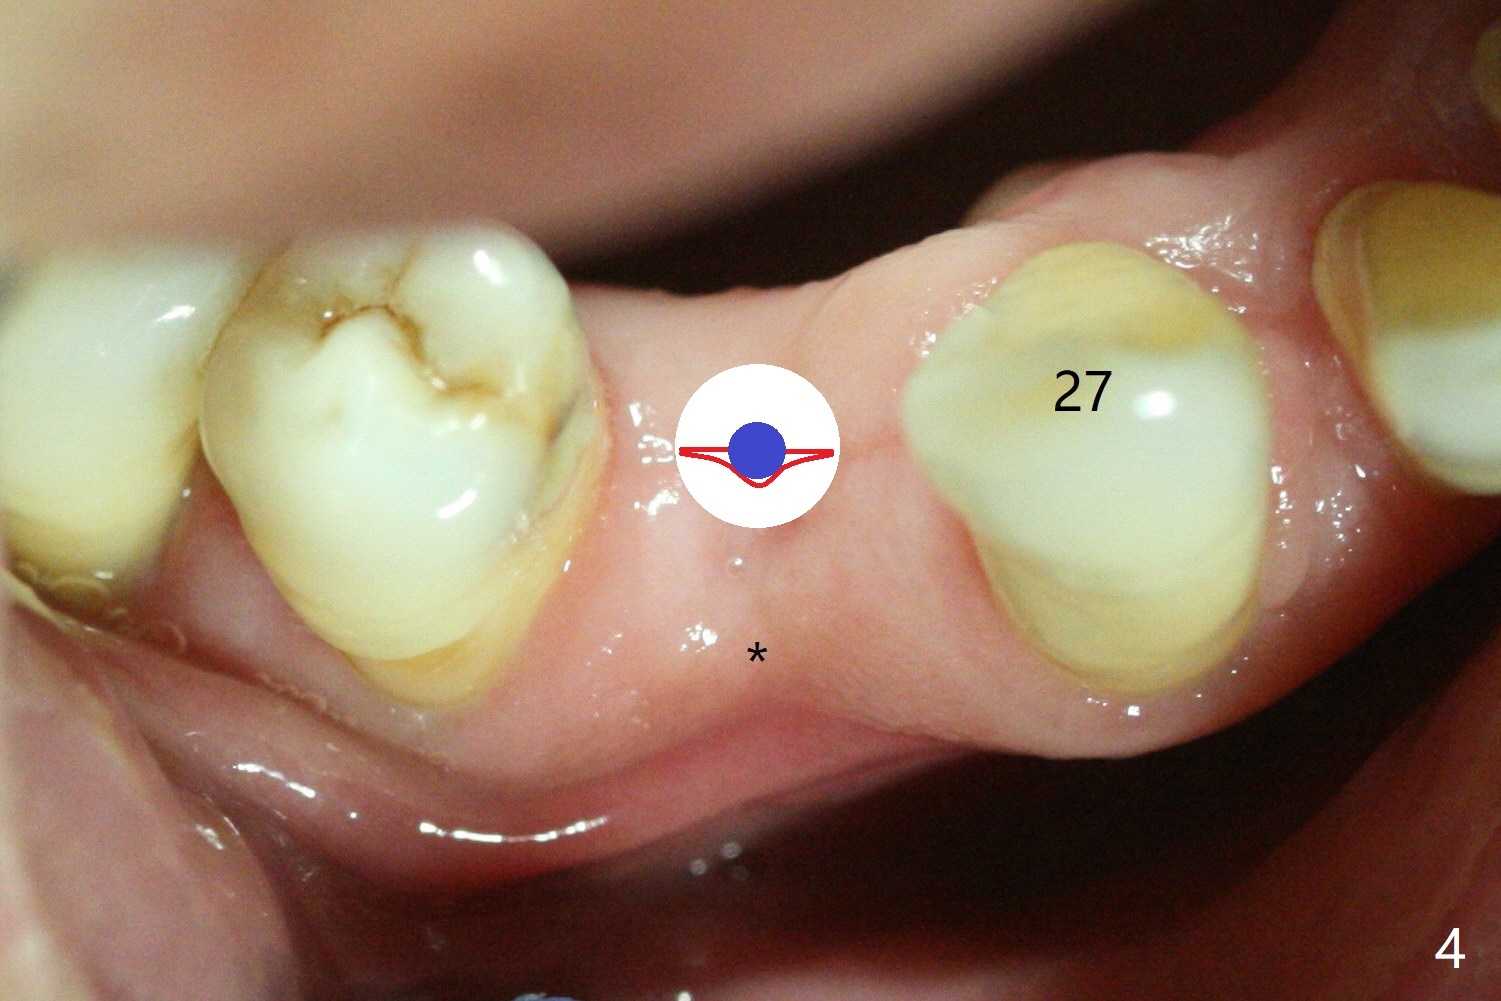

(Fig.3 red line). The buccal bone (Fig.4 red curved line) is

being expanded using a small DIO bone expander (blue circle). The buccal